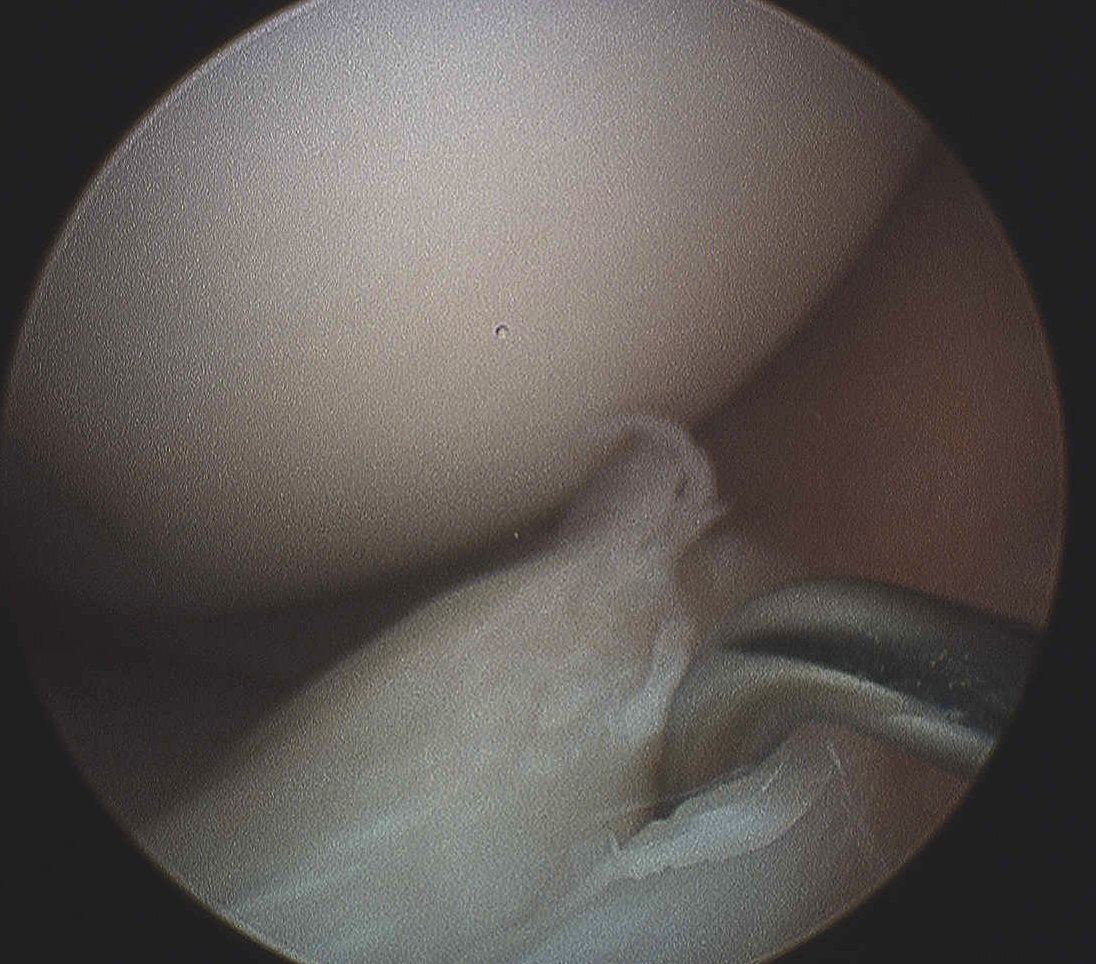

4. Meniscal Root Repair

Definition

- tear of insertion of posterior horn of meniscus

- difficult to fix

- must repair down to bone

Technique

- ACL guide

- drill hole up into mensical root insertion

- use suture passer to secure meniscal root

- retrieve sutures down through bone tunnel in tibia

- tie over screw post